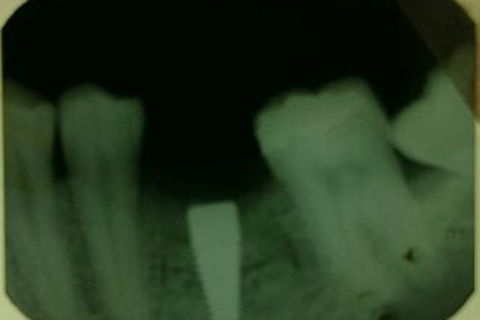

Paciente masculino. Sugerimos expansão cirúrgica e instalação imediata de implante pela técnica Split Creast.

Fotos do caso